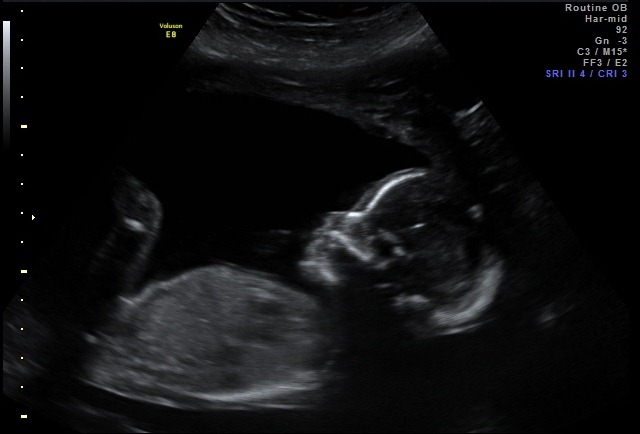

Appointment Summary: I had my OB appointment on Thursday and everything looks great! The heartbeat was right on target and the baby is measuring right where it should be! Yesterday was my big 2nd trimester ultrasound! We were able to see the baby moving around in there! It was pretty amazing to witness and I got a little teary-eyed watching it! Its heart was beating strong and he/she was practicing swallowing which is great for development. ![]()

Right now, my little baby weighs 12 ounces!